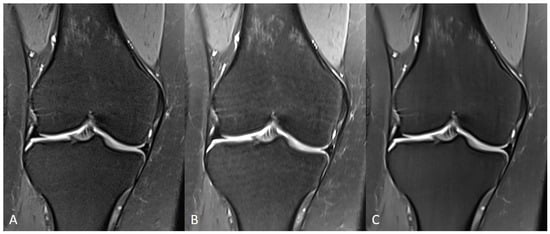

3.1. Assessment of Image Quality

| IQ | 4 (4−4) | 4 (3−4) | 0.697 | 4 (4−4) | 4 (4−4) | 0.634 | 0.002 | 0.013 |

| Artifacts | 4 (4−4) | 4 (4−4) | 0.649 | 4 (4−4) | 4 (4−4) | 0.700 | 0.180 | 0.157 |

| Edge sharpness | 4 (3−4) | 4 (3−4) | 0.883 | 4 (4−4) | 4 (4−4) | 0.792 | <0.001 | <0.001 |

| Contrast resolution | 4 (4−4) | 4 (4−4) | 0.741 | 4 (4−4) | 4 (4−4) | 0.649 | 0.257 | 0.157 |

| Noise | 4 (3−4) | 4 (3−4) | 0.897 | 4 (4−4) | 4 (4−4) | 0.651 | <0.001 | <0.001 |

| Clarity of anatomic structures | 4 (4−4) | 4 (4−4) | 0.747 | 4 (4−4) | 4 (4−4) | 0.889 | 0.317 | 0.564 |